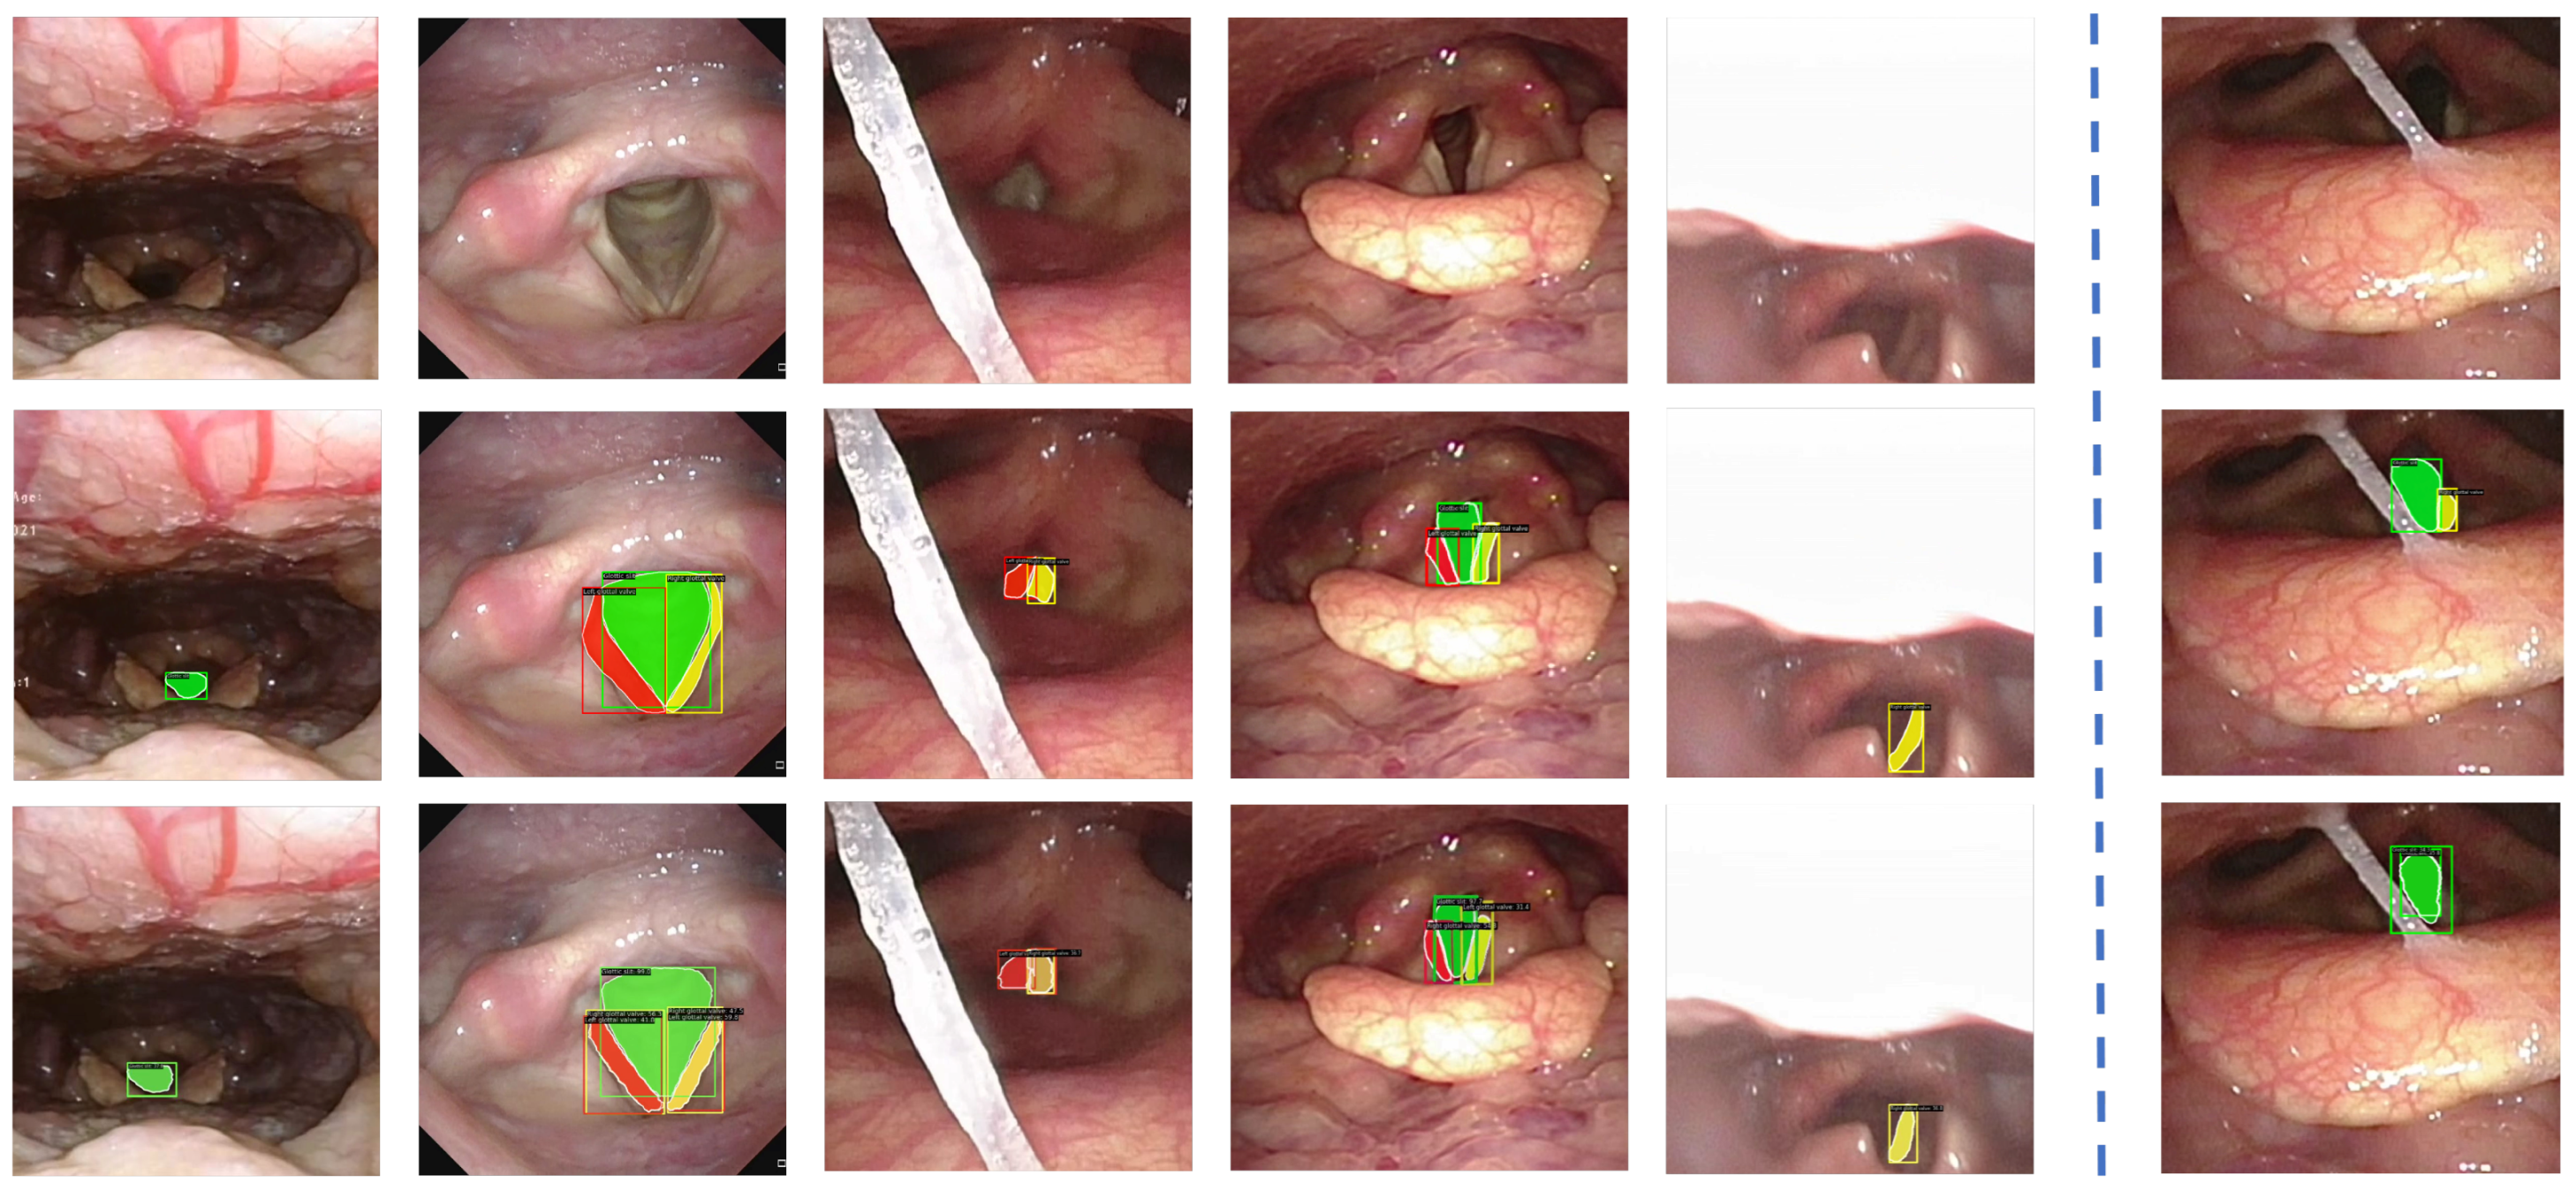

- Phantom 2025: To mitigate ethical constraints during the initial development stage, we construct a synthetic dataset using our robotic NTI system. The Phantom dataset [37] is collected in a controlled laboratory setting using a fiberoptic bronchoscope equipped with real-time navigation and feedback control, with representative samples shown in Figure 6. The dataset includes 2267 training images and 479 test images. Bounding boxes are used to label general structures, such as the nose, channel, glottis, and trachea. Masks are employed to annotate structures with more clearly defined boundaries or specific shapes, including the right nostril, left nostril, glottic slit, right glottal valve, and left glottal valve, providing pixel-level accurate representations of their form and extent. These samples provide diverse anatomical representations that support early-stage model training and validation without involving human subjects.

- Clinical 2025: The Clinical dataset [37] is obtained from nasopharyngoscopy procedures conducted at the Singapore General Hospital. It comprises 82 high-definition video recordings, each obtained from a unique patient, reflecting a broad spectrum of anatomical diversity and clinically realistic imaging conditions, as exemplified in Figure 7. All procedures are conducted by board-certified otolaryngologists using commercial flexible nasopharyngoscopes to ensure procedural consistency and clinical realism. From these recordings, we extract 2683 training images with 7030 annotated structures and 1131 validation images with 3295 annotations. These images capture key anatomical landmarks, such as the nose, nostrils, epiglottis, glottic valves, and surrounding tissues, as the endoscope passes through the glottis into the trachea.